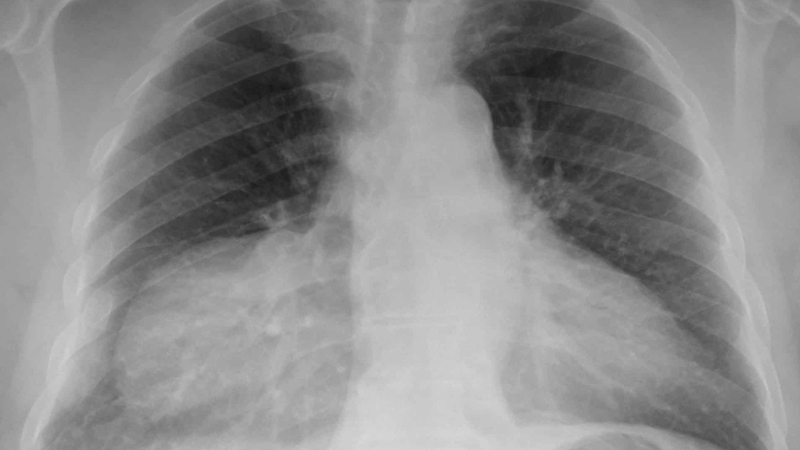

Thoát vị hoành bẩm sinh là một dị tật bẩm sinh khá phổ biến, ảnh hưởng đến sự phát triển của cơ hoành - cơ chia cách giữa lồng ngực và bụng. Bệnh có thể dẫn đến việc các cơ quan trong bụng như ruột, dạ dày chui lên phần ngực, gây ra các triệu chứng nghiêm trọng như khó thở, tím tái và khó khăn trong việc nuốt. Các triệu chứng này thường xuất hiện ngay sau khi trẻ sinh ra, đòi hỏi sự can thiệp y tế khẩn cấp để tránh biến chứng nghiêm trọng hơn.

Việc phát hiện sớm và điều trị kịp thời cho bệnh thoát vị hoành bẩm sinh là vô cùng quan trọng. Trẻ sơ sinh cần được thăm khám kỹ lưỡng ngay sau khi chào đời để phát hiện các dấu hiệu bất thường của dị tật này. Một khi đã xác định, phương pháp điều trị chủ yếu là phẫu thuật để sửa chữa cơ hoành và đưa các cơ quan trở lại vị trí bình thường của chúng. Việc can thiệp sớm không chỉ cải thiện đáng kể khả năng sống sót của trẻ mà còn giúp giảm thiểu các rủi ro về mặt phát triển lâu dài của trẻ